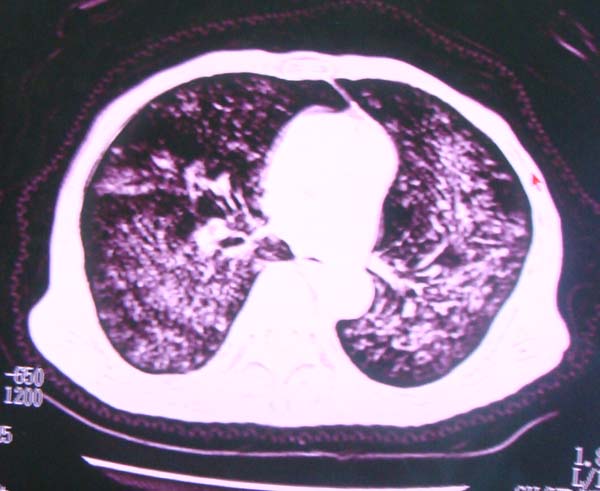

以下是引用zhangzhongshou在2008-2-15 22:25:00的发言:[br]片子照得不清,基本考虑1、细支气管肺泡癌2、亚急性血行播散型肺结核。请结合临床。片子细节显示不清,无法提供进一步意见。

以下是引用杀毒软件在2008-2-15 22:34:00的发言:[br]小叶中心性肺气肿。两肺弥漫性病变,肺泡微石病,过敏性肺炎,尘肺2期,特发性肺纤维化都有可能。[br]不象肺泡癌。